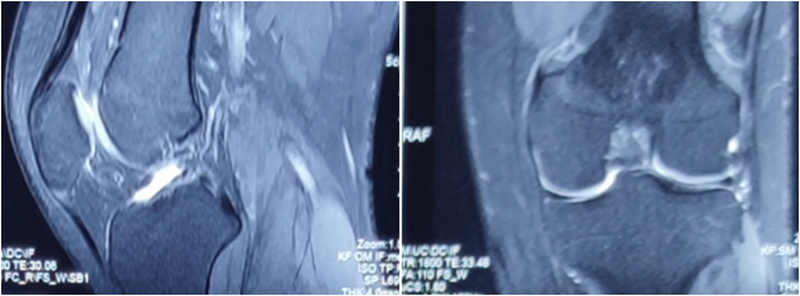

术后MRI

MRI检查评估ACL-R术后——韧带连续性信号好、方向好、愈合快,没有Cyclops综合征。

2019年关于前叉保残重建的荟萃分析研究,纳入了2000至2018年12月10日,随访时间超过1年的11篇文章,保残重建能够促进移植物血供和滑膜覆盖,但对膝关节稳定性和术后效果与单纯前叉韧带重建的效果无明显差异。